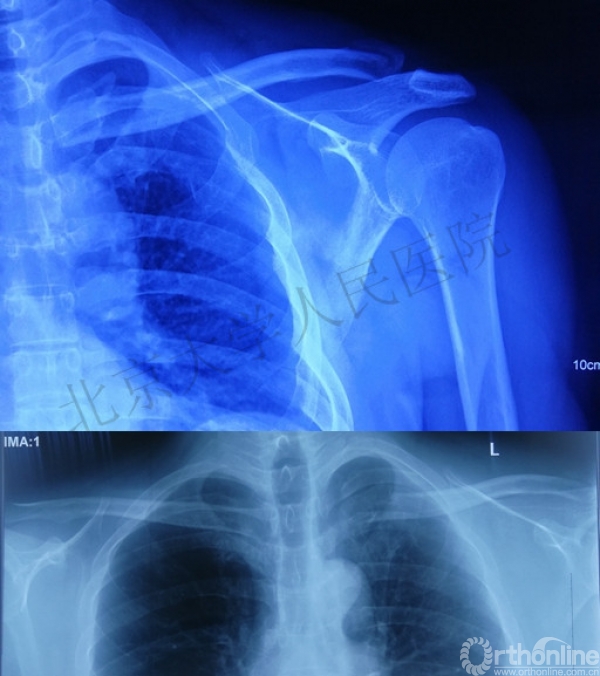

43岁男性,骑电动车时发生交通事故摔伤左肩及左胸

查体:左胸壁后方压痛;左锁骨近端区域凸起,压痛(+),远端未见明显畸形,压痛(+),锁骨轴向叩痛(+)

影像学检查—X线

你是否认为容易漏诊?

1.创伤性漂浮锁骨(左侧)

(1)锁骨远端骨折

(2)锁骨近端骨折

(3)胸锁关节脱位

2.左侧肋骨骨折(2-3后肋)

3.软组织损伤(左肩部及胸壁)